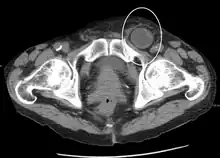

An incarcerated inguinal hernia as seen on cross sectional CT scan

A frontal view of an incarcerated inguinal hernia (on the patient's left side) with dilated loops of bowel above.